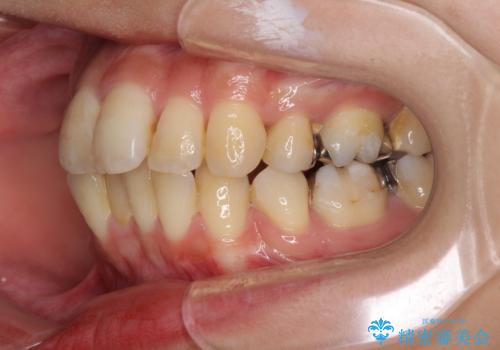

- 抜歯矯正の後戻りで前歯が突出してきていることを気にして来院された患者様です。

口元の突出感を改善するにあたり、抜歯矯正は行うことができないため、奥歯の後方移動とIPR(歯と歯の間を削る)により達成することとしました。

再度後戻りしたときに対応しやすいよう、インビザラインにて矯正治療を行うこととしました。